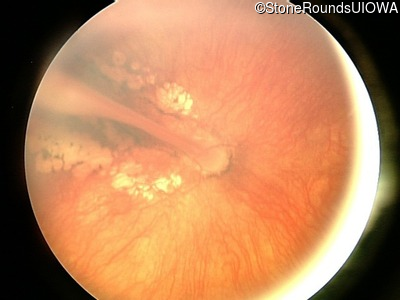

Fundus Photography - Right - 20/125

Exemplar